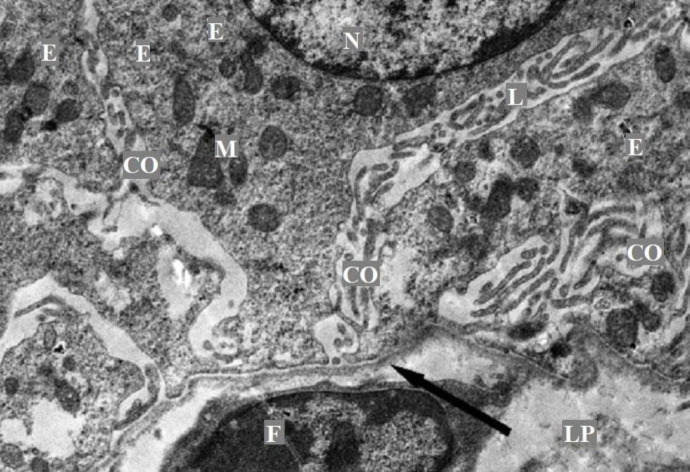

Currently, studies devoted to establish the anatomical and histological patterns of the internal organs organization in animals depending on their species and breed, as well as conditions of detention are the most relevant. The liver morphology in representatives of the ruminant family has not been sufficiently studied. Questions regarding the micro- and ultra-structural organizations of the gallbladder wall remain open. The aim of the study was to establish the ultra-structural organization features of the gallbladder mucous membrane of an Anglo-Nubian goat. The material for the study was the gallbladder wall's fragments of an adult Anglo-Nubian goat. Further processing of the obtained samples was carried out to acquire histological preparations. Ultra-thin sections were photographed in a Jem-1011 electron microscope at magnifications of 2,500 - 3,000. It was found that the gallbladder mucous membrane of an Anglo-Nubian goat is formed by the epithelial layer and its own lamina. The epithelial layer is represented by a single-layer prismatic epithelium. The nuclei are light, with clear contours. The apical surface of epithelial cells forms microvilli and the cytoplasm of the apical pole of cells contains many electron-dense secretory granules. The lateral surfaces of the cells in their apical part are interconnected by tight contacts. The lamina propria is formed by loose connective tissue containing many blood vessels and nerve fibers. Referring to the scientific literature describing possible pathologies of the gallbladder, we can conclude that the picture presented in the results generally corresponds to the position of the gallbladder without pathologies.